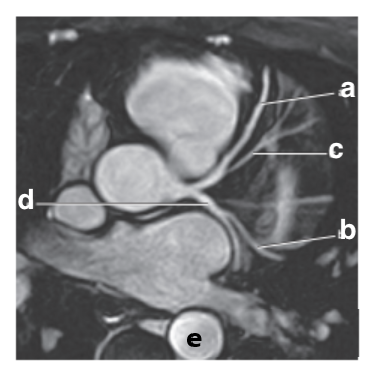

What is letter a ?

Left atrium

What is letter b ?

Left ventricle

Which letter is the Right coronary artery ?

c

Bicuspid valve / LT AV valve